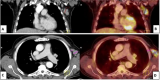

PET/CT显示在原发性醛固酮增多症患者中的应用前景

Pentixafor是2015年开发的一种配体,可与细胞表面的CXCR4受体结合。当与核素Ga-68结合时,产生的放射性示踪剂可以在PET成像上显示异常的CXCR4活性。